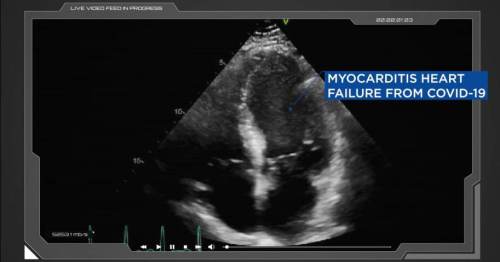

“FDA Panel Rejects Pfizer Booster Shot for Ages 16-65 Over Increased Risk of Heart Inflammation”

“The panel voted 16-2 to reject extra doses of experimental vaccine, citing insufficient data from incomplete clinical trials and the potential risk of heart inflammation – especially among young men.